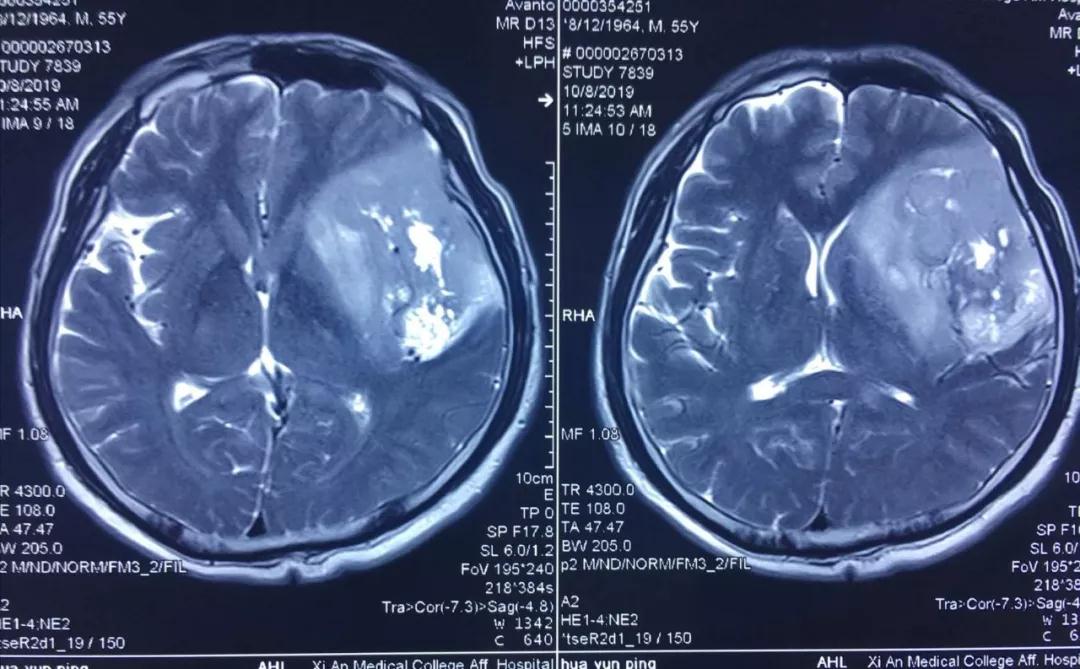

患者李某,今年55歲,因近年出現(xiàn)間歇性面部抽搐,一直未給予重視,近來發(fā)作頻繁,經(jīng)朋友建議在外院行頭顱核磁檢查,發(fā)現(xiàn)顱內(nèi)巨大占位性病變,病變位于左側(cè)額、顳和深部腦島葉,達(dá)8.5?5.5?3cm,且侵犯語言功能區(qū),顱內(nèi)占位效應(yīng)明顯,中線偏移1cm,且腫瘤已經(jīng)瀕臨腦疝邊緣,如不及時(shí)進(jìn)行手術(shù)干預(yù),隨時(shí)有腦疝可能,危及患者生命。

經(jīng)多方了解后,在朋友的推薦下,患者慕名來到西安國際醫(yī)學(xué)中心找到了腦科醫(yī)院高國棟院長,高院長帶領(lǐng)以賀世明主任為首的神經(jīng)外科團(tuán)隊(duì),對患者的病情及治療方案等進(jìn)行討論,憑借多年的臨床經(jīng)驗(yàn),結(jié)合患者影像結(jié)果判斷為顱內(nèi)膠質(zhì)瘤,并建議盡快實(shí)施手術(shù)切除。